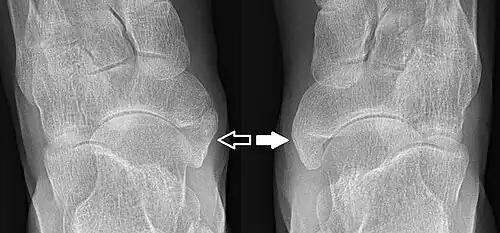

-

From left to right: Type 1, 2 and 3 -

Type 2 on one foot (dark arrow) and type 3 on the other (white arrow)